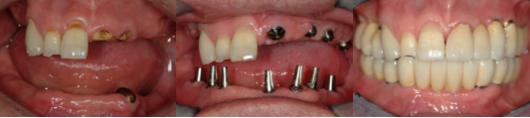

임플란트 전악고정성 보철물 : 10-14개의 임플란트를 식립하고 그 위에 고정식으로 치아보철물을 올립니다.

임플란트 오버덴쳐 : 아랫턱 2-4개, 윗턱 4-6개의 임플란트를 식립하고, 틀니가 식립된 임플란트로부터 지지 및 유지효과를 얻습니다.

임플란트 치료는 크게 수술 단계와 보철 단계로 나누어집니다.

수술 단계는 뼈 안에 임플란트를 식립하는 과정입니다. 수술 규모가 작으면 부분마취만으로 수술하며, 규모가 클 경우 전신마취 하에 수술하기도 합니다.

보철 단계는 식립된 임플란트 위에 치아 구조물을 올리는 과정입니다. 임플란트가 뼈와 잘 고정되었다고 판단된 이후에 진행합니다. 치료 규모에 따라 차이가 있을 수 있으나, 대략 1주 1회의 내원을 기준으로 1-2개월의 기간이 필요합니다.